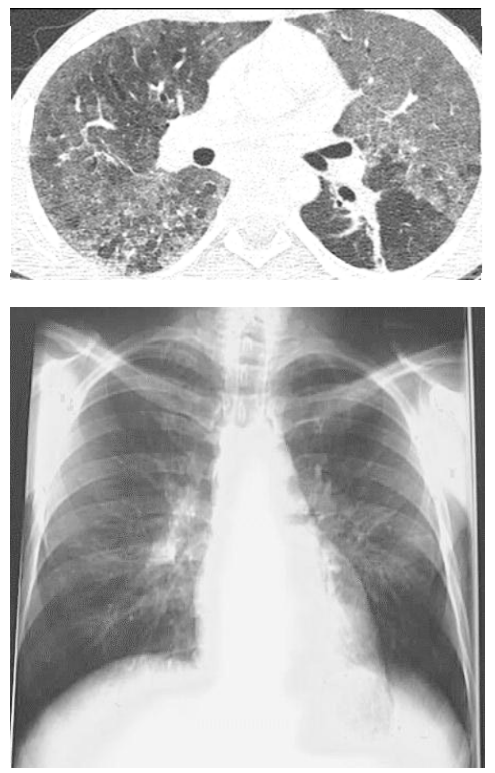

Um homem de 36 anos de idade, cabeleireiro, tabagista (cinco anos/maço), evoluiu progressivamente, durante o último ano, com dispneia e “sensação de afogamento”. Procurou diversos serviços durante esse período, tendo sido diagnosticado com síndrome respiratória gripal por covid duas vezes, devido aos achados tomográficos, porém com sorologia e PCR negativos em ambos os momentos. Realizou, também, testes para tuberculose e pneumocistose, ambos negativos. No momento, sem queixas ao repouso e saturando 94% em ar ambiente.